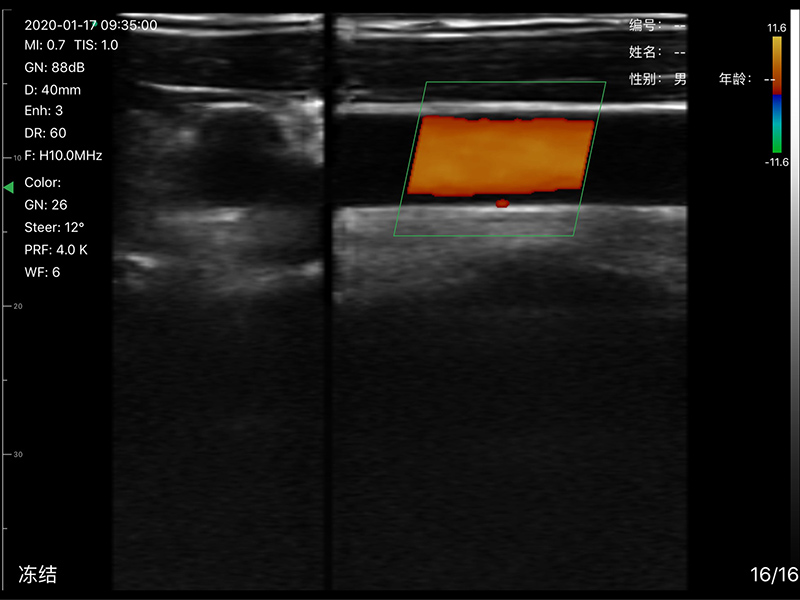

• 探头频率:7.5/10MHz

• 扫描深度:20/40/60/100mm,可调

• 显示模式:B、B/M、CF、PW、PDI

• 穿刺辅助功能:平面内穿刺引导线功能,

平面外穿刺引导与血管自动测量功能,针尖显影增强功能